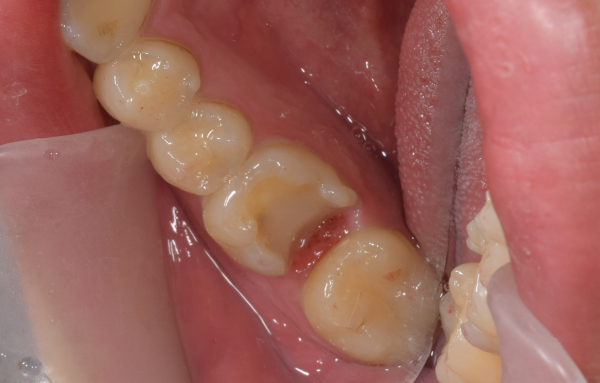

治療前の状態・主訴

患者様は30代男性の方で、定期検診で来院されました。

見た目や痛みなど、特に症状は認められませんでしたが、レントゲン写真撮影にて、元の被せ物の下に隠れた虫歯の影が認められました。

治療後の様子

型取りから約2週間後に、被せ物をセットしました。

今回は、e-maxという天然歯に近い色調と透明感があるセラミック素材を使用しました。

金属アレルギーの心配がなく、今回も下のように天然歯に近い被せ物をセットすることが出来ました。

この患者様は、治療後に痛みもなく経過しております。